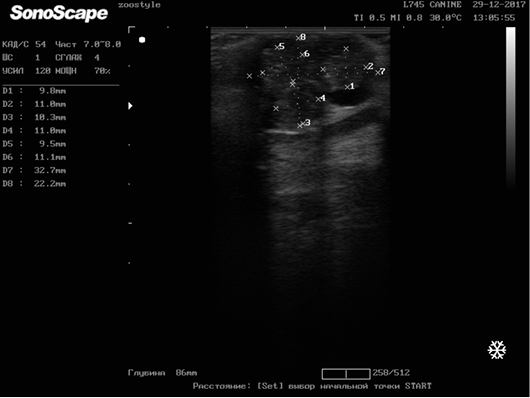

Figure 5

Metastasis of breast cancer in the liver parenchyma. Doggess, breed American Bulldog, at the age of 11.5 years.